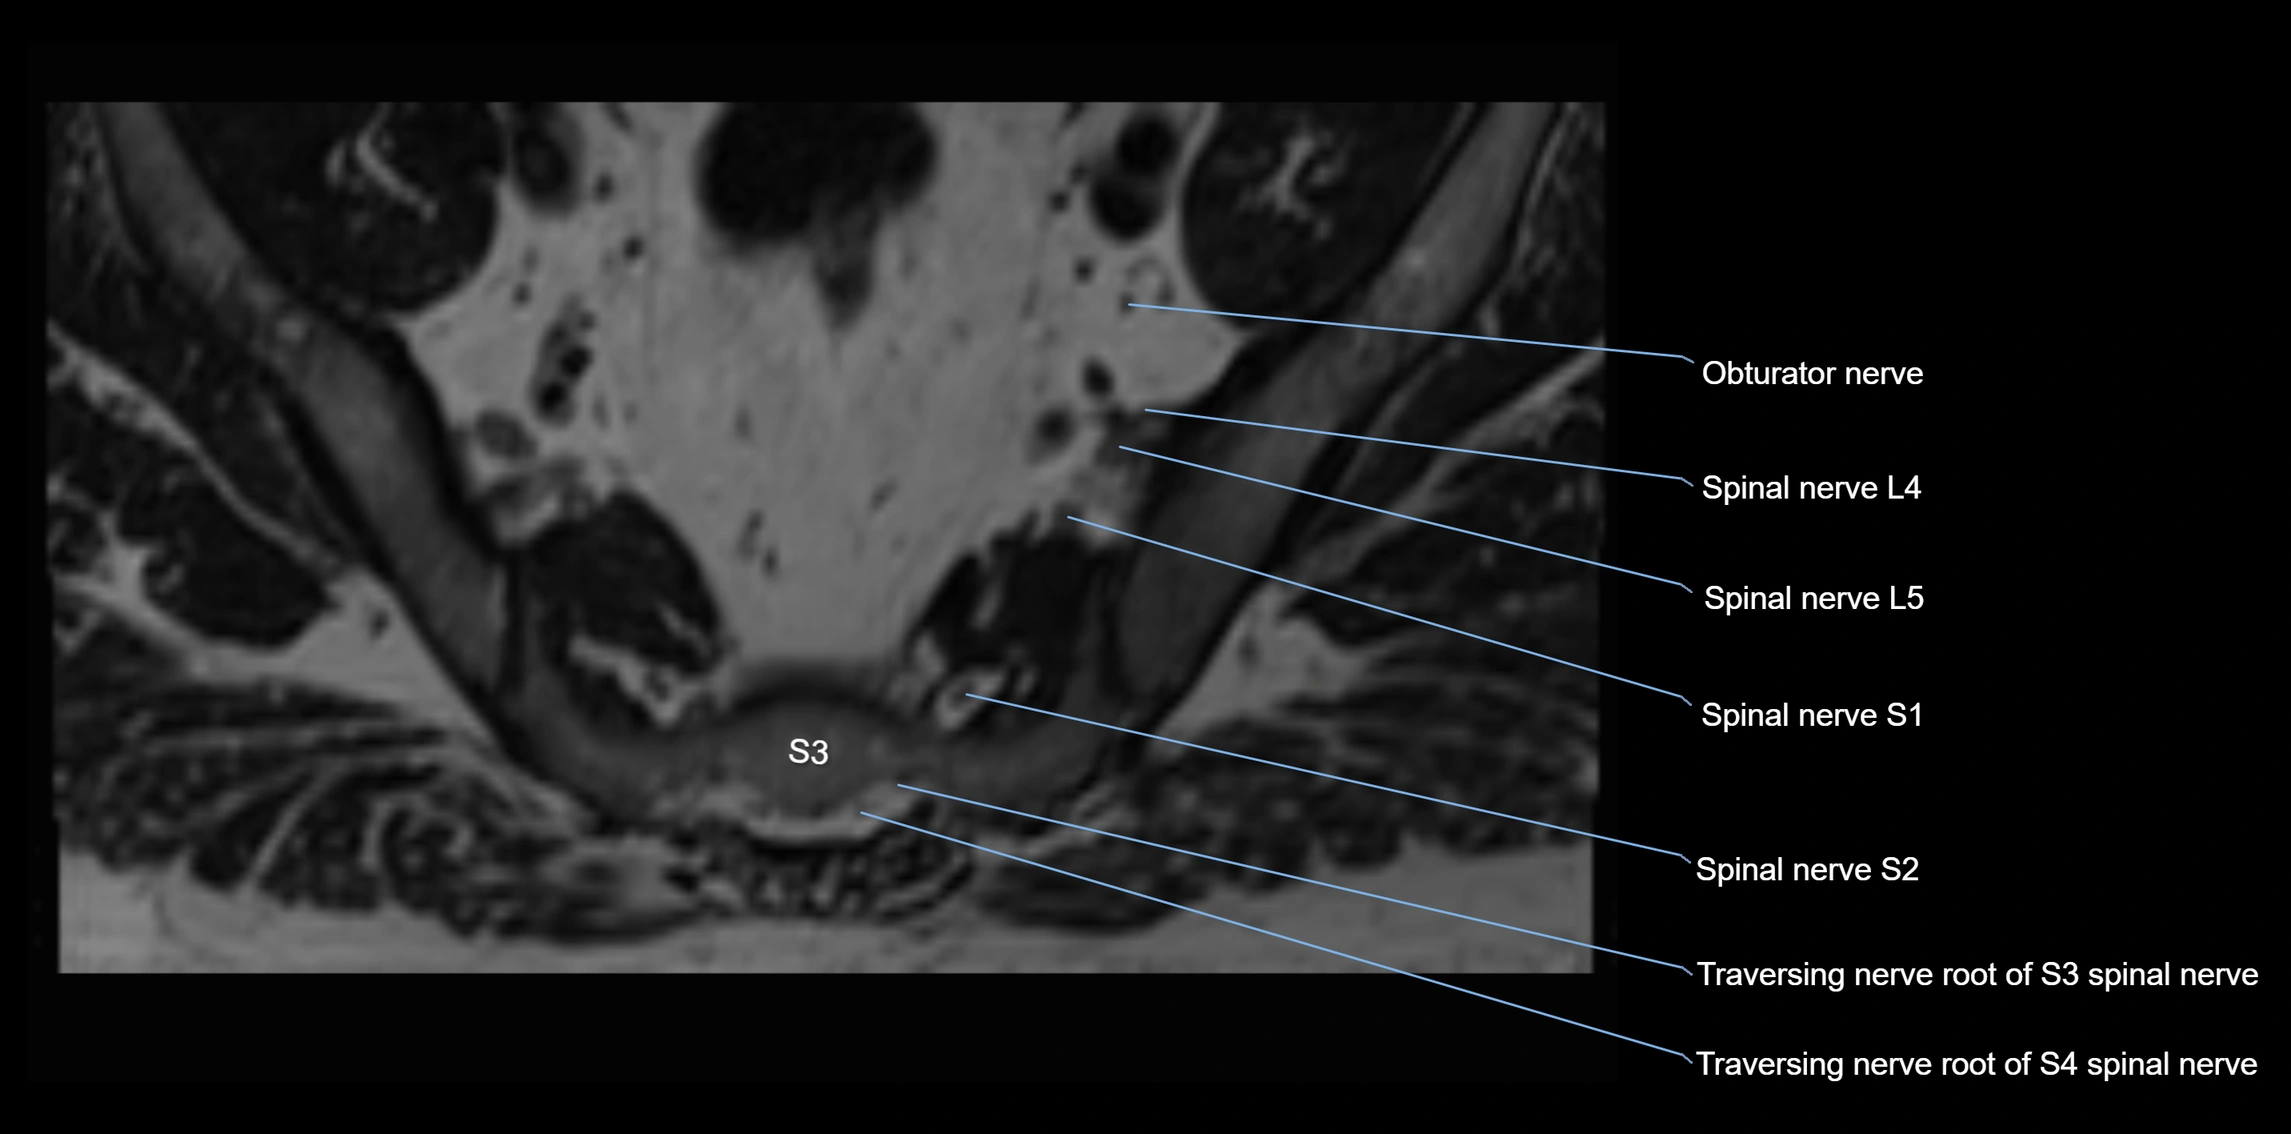

MRI Appearance

T1-weighted images:

• Nerve appears as a very thin low-to-intermediate signal intensity structure

• Surrounded by bright fat, aiding visualization

T2-weighted images:

• Nerve shows intermediate to mildly hyperintense signal compared to muscle

• Pathological involvement appears brighter

STIR (Short Tau Inversion Recovery):

• Normal nerve appears dark

• Inflamed or entrapped nerve appears bright hyperintense

T1 Fat-Sat Post-Contrast:

• Normal nerve enhances minimally

• Pathologic nerve (neuritis, entrapment, tumor infiltration) shows focal or diffuse enhancement

3D T2 SPACE / CISS:

• Nerve appears intermediate to mildly hyperintense compared to muscle

• Surrounded by bright fat or CSF, improving visualization

• Best sequence for mapping small pelvic nerves such as the anococcygeal